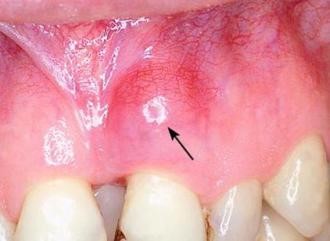

Свищ

Может быть как внутренним, так и давать дефект лица. Через него выходят гнойные выделения. Наличие свища после лечения говорит о его неэффективности. В некачественно запломбированном зубе размножаются бактерии, провоцируя воспаление. Лечат свищ антибиотиками, антигистаминами. Эффективно местное лечение раствором соли. Лечение долгое и требует тщательного контроля. Врач старается сделать все, чтобы спасти зуб. Если врач действовал правильно, свищ закрывается сам. Иногда приходится применять оперативное вмешательство. При возникновении свища очень важно оперативно обратиться к стоматологу.